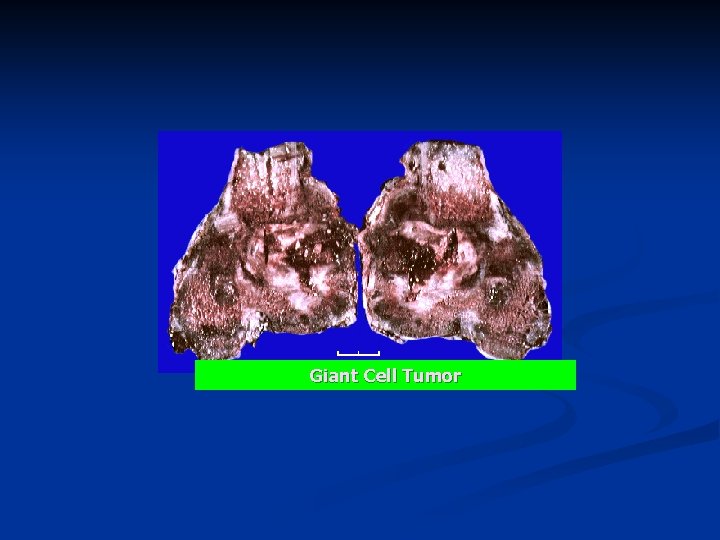

Giant Cell Tumor An aggressive benign tumor n Composed of : n well vascularized stroma n plump, spindly, and oval tumor cells n multinucleated tumor giant cells n n Over the age of 20: most commonly in the third decade of life n slight female preponderance n

n The skeletal location: n 50% of cases occur near the knee n most commonly in the distal end of the femur or the upper end of the tibia. n The x-ray picture : Large, eccentric, oval, n Radioluscent destructive lesion centered in the epiphysis, n Cortical erosion and thinning, n Expanding the bone contours without a border. n

Giant Cell Tumor

Giant Cell Tumor